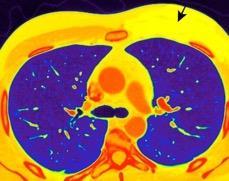

Derrame pleural..33,3% Derrame bilateral.26,7% Ganglios mediastínicos e hiliares..66,7%..

No hiliares

Okada F et al. Chest HRCT findings in acute transformation of adult T-cell lymphoma/leukemia. Eur Radiol 2015

Vidrio deslustrado 60%. Consolidación 33,3% Nódulos…33,3%